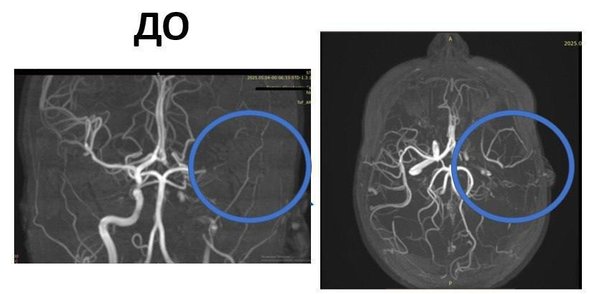

По словам врачей, во время купания мама заметила, что у дочери появилась слабость в правой руке и ноге. В следующий момент нарушилась речь и появилась асимметрия лица. Семья быстро вызвала скорую и школьницу уже в тяжелом состоянии бригада скорой помощи экстренно доставила в клинический центр имени Рошаля. МРТ подтвердила первые подозрения врачей на обширный ишемический инсульт левого полушария мозга.

фото: vk.com/roshal_kids